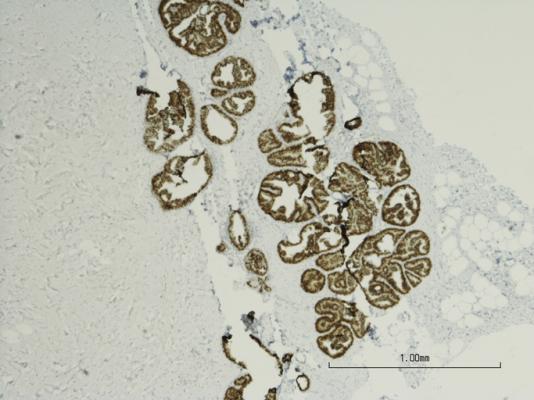

Microscopic photo of a professionally prepared slide demonstrating breast tissue with ductal carcinoma in situ (DCIS). Immuhistochemistry of estrogen receptor positive. Micrograph of breast cancer. Slide shows corresponding length of 1 mm. Getty Images

DCIS is a condition where cells lining the milk ducts have started to turn into cancer cells but have not spread into other parts of the breast. DCIS is often picked up by breast screening and affects tens of thousands of women in Europe each year. Only a proportion of DCIS cases will progress into invasive cancer and little is known about which cases will progress, so the treatments available to patients are very similar to treatments for invasive breast cancer.